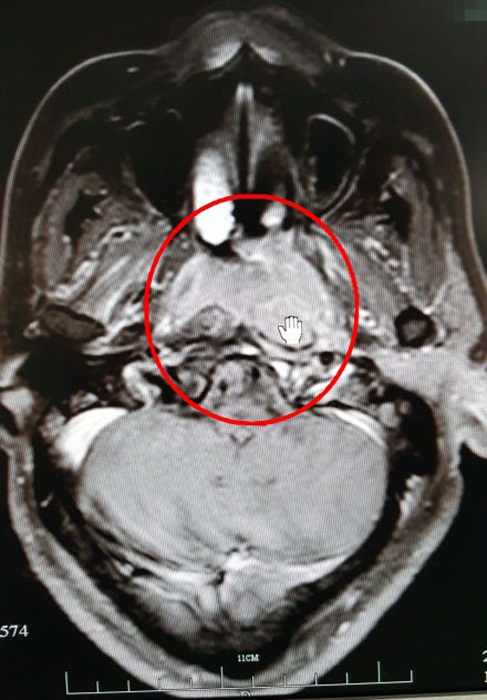

放療前的CT影像(紅圈處為病灶)